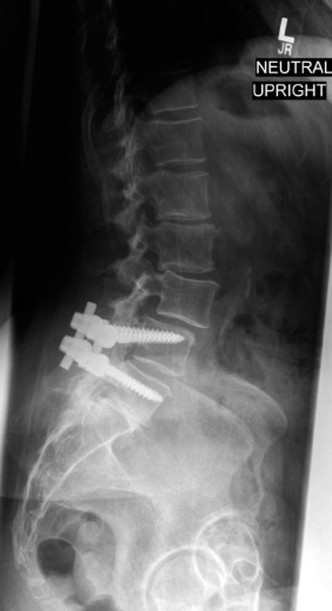

The inadequacy of modern surgical techniques to reduce or eliminate adjacent segment degeneration? CASE 16 A 51-year-old fireman whose primary complaint was chronic low back pain and right-sided leg pain underwent an L4–5 lumbar laminectomy and posterior instrumented spinal fusion for a diagnosis of L4–5 lumbar stenosis and degenerative spondylolisthesis. During surgery, bilateral pedicle screw instrumentation is placed at the L4 and L5 levels. There were no apparent complications and intraoperative radiographs including anteroposterior and lateral views were unremarkable. Immediately following surgery, the patient reported substantial relief of his right lower extremity pain, numbness, and weakness but now has difficulty sitting and walking due to new onset of severe left lower extremity pain, numbness, and weakness. Physical examination reveals a positive straight leg

raise test on the left side, dense numbness in the left great toe, and new focal weakness in left ankle and great toe dorsiflexion.

The correct answer is (D). The patient has new severe postoperative sciatica and a new neurological deficit, so simple observation is not appropriate. Intraoperative radiographs revealed no apparent abnormalities, so repeated plain radiographs are unlikely to provide additional useful information. An MRI study would be indicated if the concern was for a potential postoperative epidural hematoma, but with complete relief of pain and symptoms in one lower extremity, a hematoma becomes less likely. The most likely etiology is direct nerve root impingement from a malpositioned pedicle screw. A CT scan with sagittal and coronal reconstructions is most likely to identify this problem.

Imaging of this patient shows an inferomedial left L5 pedicle breach and likely impingement of the adjacent nerve root by the pedicle screw. What is the next most appropriate step in managing this patient?

During surgery, a malpositioned left L5 pedicle screw appears to be directly impinging upon the adjacent nerve root. Despite multiple attempts to reposition the screw, stable fixation cannot be achieved, and the surgeon elects to remove all implants and perform a noninstrumented in situ fusion instead. Following surgery, the patient should be advised that, relative to an instrumented fusion, a noninstrumented fusion has:

The correct answer is (D). Noninstrumented so-called “in situ” fusions are associated with a significantly lower fusion rate compared with instrumented spinal fusions. Despite this fact, both in situ and instrumented fusions achieve comparable short- and long-term clinical outcomes, although some investigators believe that the long-term increased nonunion rate of in situ fusions results in overall marginally worse outcomes in terms of pain and disability scores. Of note, the literature suggests that pedicle screws with 2 mm or less of a cortical breech are unlikely to be associated with significant clinical problems, whereas medial or caudal breeches of 5 mm or more are considered more likely to be associated with neurological symptoms. Nevertheless, in the setting of a new neurological deficit in the immediate postoperative period, early radiologic assessment and treatment of potentially malpositioned pedicle screws are recommended. Objectives: Did you learn...? Identify the signs and symptoms of a malpositioned lumbar pedicle screw?